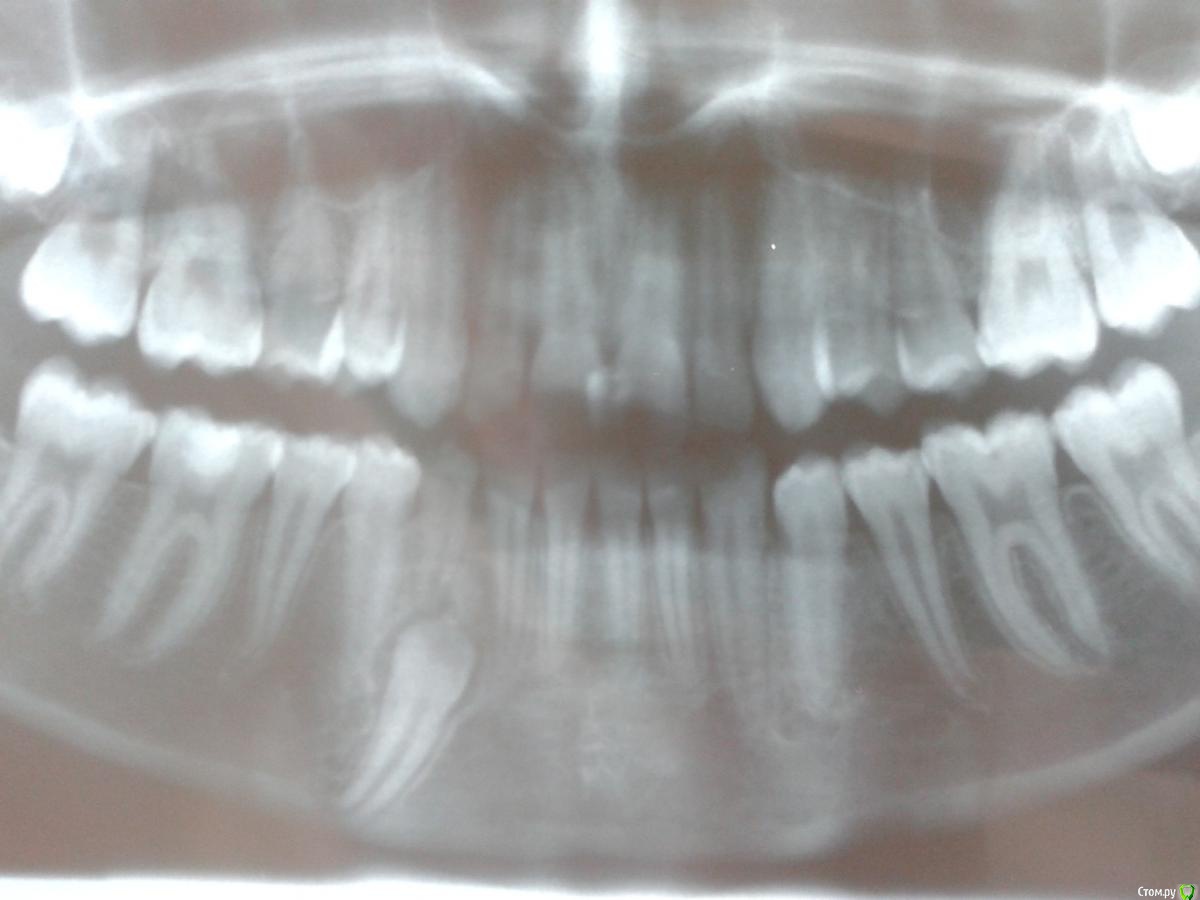

sgeorge Опубликовано 24 апреля, 2015 Поделиться Опубликовано 24 апреля, 2015 Добрый день, коллеги! Девочка 15 лет. Как быть ?Мягкова.bmp Ссылка на комментарий

sgeorge Опубликовано 24 апреля, 2015 Автор Поделиться Опубликовано 24 апреля, 2015 А это синимок 2012 года. Извините за качество, снимок на пленке Ссылка на комментарий

sgeorge Опубликовано 24 апреля, 2015 Автор Поделиться Опубликовано 24 апреля, 2015 Как-то криво прикрепились, сорри.Думаю, что с таким крючком на апексе ортодонтия отпадет? Тогда стоит ли удалять в настоящий момент или дождаться завершения роста челюсти? Ссылка на комментарий

krokomot Опубликовано 24 апреля, 2015 Поделиться Опубликовано 24 апреля, 2015 Клык то молочный во рту, без ортодонтии все равно не обойтись так что можно попробовать зуб вертикально почти стоит, только кортикалку желательно бы удалить по ходу выдвижения (постепенно). На стрелке думаю одонтома при раскрытии убрать. Ссылка на комментарий

CToMaToJlor Опубликовано 24 апреля, 2015 Поделиться Опубликовано 24 апреля, 2015 А мне кажется, вытянуть не получится. Удаление , ортодонтия, имплантация. Там же крюк на корне. Ортодонт не возьмется. Имхо Ссылка на комментарий

sgeorge Опубликовано 26 апреля, 2015 Автор Поделиться Опубликовано 26 апреля, 2015 Жалобы на самопроизвольные мигрирующие боли верхней и нижней челюсти справа в течение последней недели. Прикус ортогнатический, на месте 43 молочный 83, подвижность 1 степени. Множественный кариес, гигиена полости рта неудовлетворительная. Ссылка на комментарий

sgeorge Опубликовано 29 апреля, 2015 Автор Поделиться Опубликовано 29 апреля, 2015 Значимость клыка вполне ясна. Сильно смущает загнутая верхушка корня, позволит ли это переместить зуб на столь немаленькое количество милиметров Ссылка на комментарий

krokomot Опубликовано 29 апреля, 2015 Поделиться Опубликовано 29 апреля, 2015 Значимость клыка вполне ясна. Сильно смущает загнутая верхушка корня, позволит ли это переместить зуб на столь немаленькое количество милиметровПочему это вас смущает? Когда ортодонт корпусно перремещает зуб, площадь костного сопротивления гораздо больше, чем какой-то крючок, крючок будет мешать удалению, но не как не перемещению. 2 Ссылка на комментарий